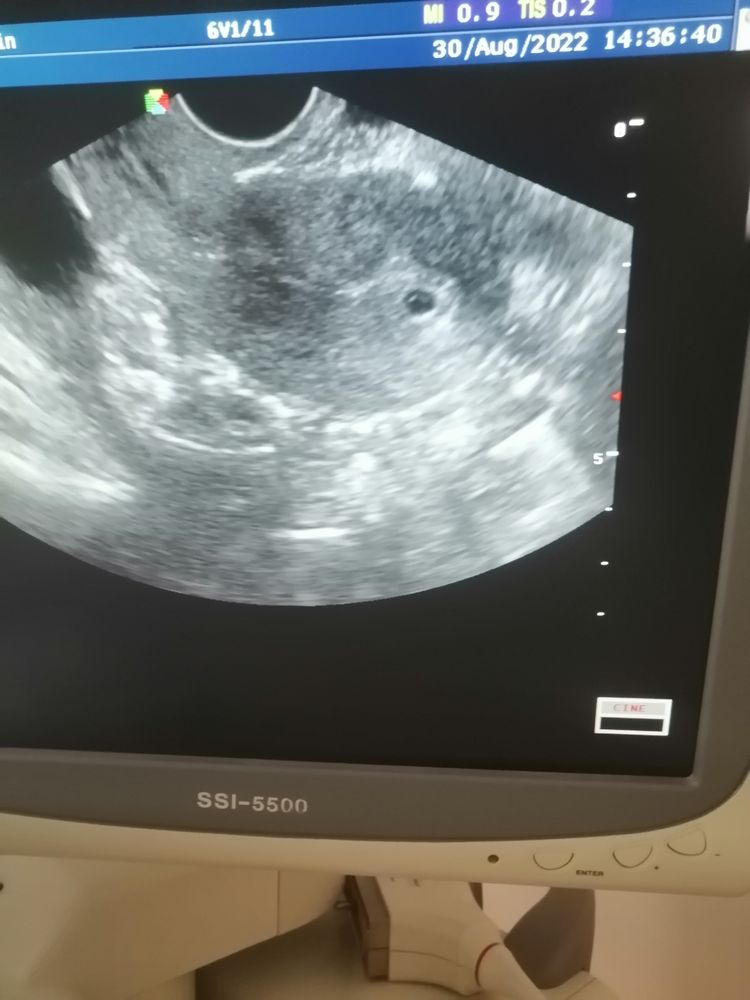

20дпп результаты моего узи

Я БЕРЕМЕННА !

20дпп,сходила я сегодня на узи... Плодное яйцо 4,5мм..Срок по акушерским данным 4 недели 4дня...плодное яйцо в матке 🥰🙏...

PS:a внутри что-то виднеется, что это может быть 🤷♀️ 🤔